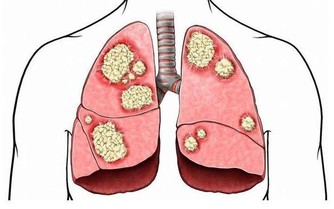

維生素C還可以清除自由基,能使人體免受自由基的侵害,從多方面提高人體抗病能力,在流行性病季節適當補充維生素C能有效預防感冒,和流行病。